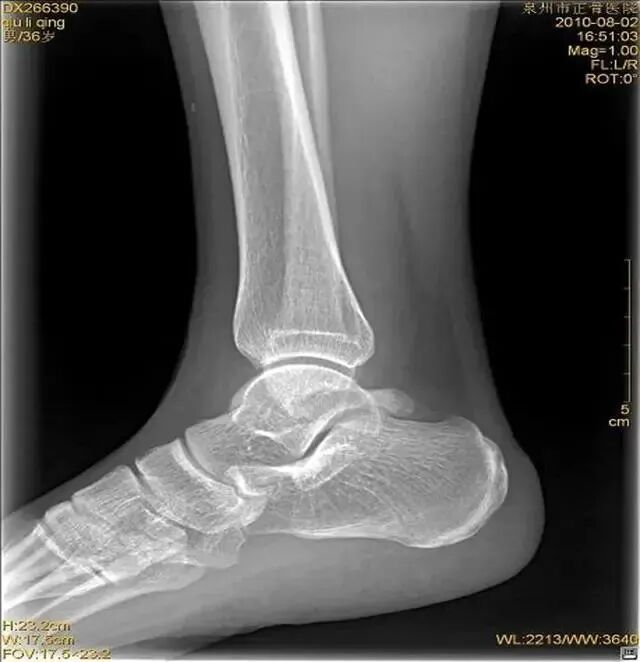

踝关节扭伤

是最常见的踝部损伤之一,据估计,全世界范围内每天每1万人中就有1人踝关节扭伤,扭伤可发生于运动员,也常见于普通人。

扭伤机制

距骨在踝穴内有无倾斜,会通过影响关节面接触面积而影响关节所受应力的大小。有轻度倾斜,关节面所受到的应力会因为承重面积变小而明显增加。

旋后位扭伤最为常见;

距骨体前宽后窄,当踝关节背屈时,其宽部进入踝穴,能防止踝关节向后脱位;当跖屈时,其窄部进入踝穴,则关节不稳,易向侧方活动。